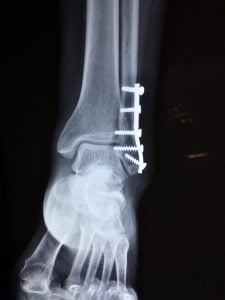

yardımcı olur. - Cerrahi Müdahale: Bazı kırıklar, kemiklerin uygun bir şekilde hizalanması ve sabitlenmesi için

cerrahi müdahale gerektirebilir. Özellikle açık kırıklar veya kemiklerin yer değiştirdiği kırıklar

cerrahi olarak tedavi edilebilir. Cerrahi müdahale, kırığın doğru şekilde iyileşmesini sağlamak için

plaklar, vida ve çiviler gibi medikal cihazlar kullanılarak gerçekleştirilir. Cerrahi tedavi genellikle

daha karmaşık kırıklar için gereklidir ve iyileşme süreci diğer yöntemlere göre daha uzun olabilir.